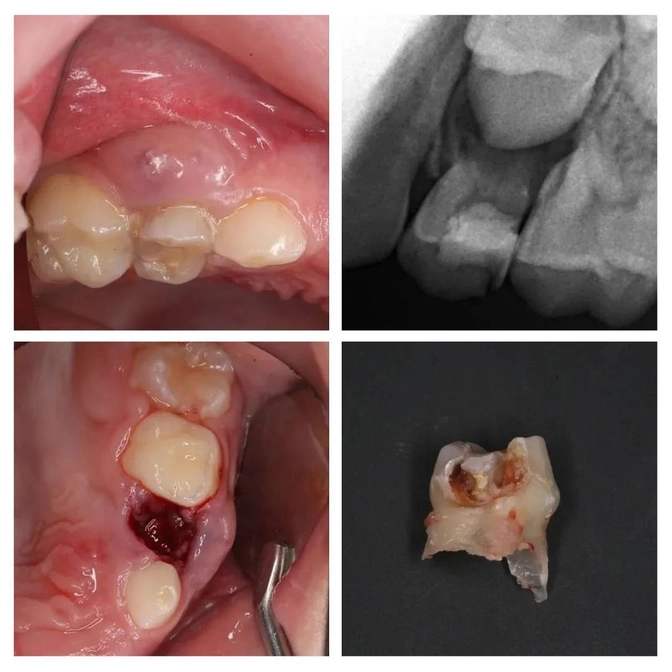

Пациенту 7 лет.

Мама привела его лечить зубы, т.к. «четверка» уже сильно разрушена.

Сделали снимок и что видим: воспаление уже вышло за пределы зуба и поразило периодонт (связочный аппарат, который удерживает зуб на месте).

Это прямое показание к удалению молочного зуба!

Вернулись они на следующий же день.

Что вы думаете — СВИЩ❗

Зуб, естественно, удалили.